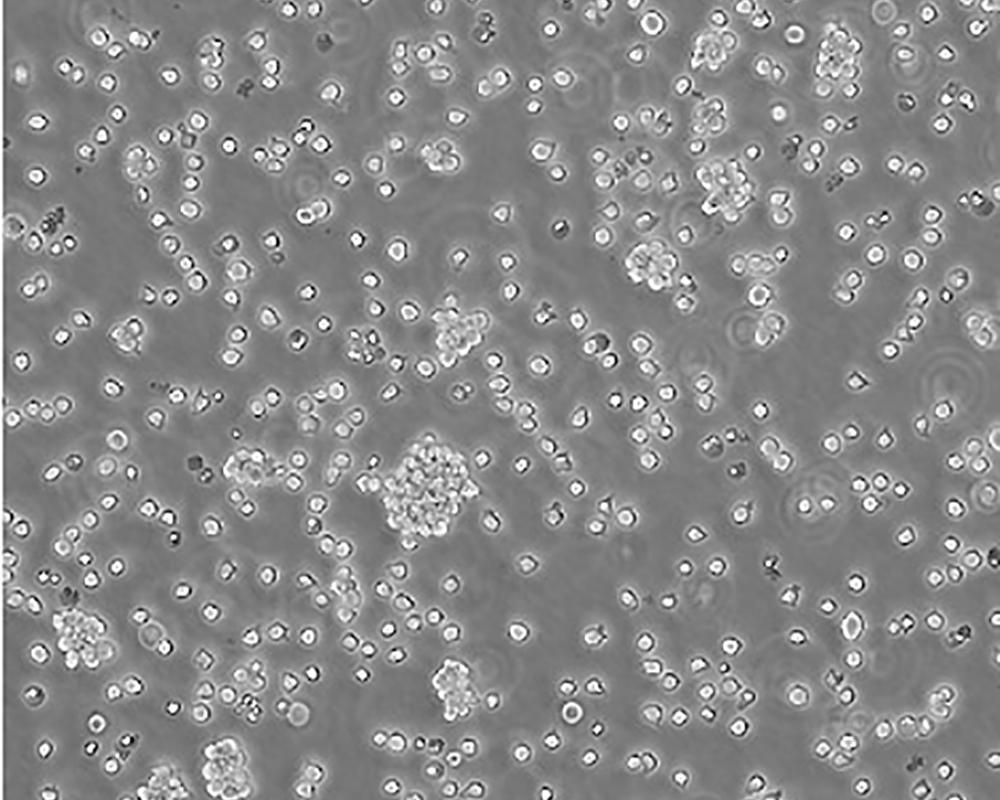

Jurkat, Clone E6-1 [Jurkat E6-1]

人T淋巴細胞白血病細胞

急性T淋巴細胞白血病;男性

suspension

lymphoblast

該細胞是Jurkat-FHCRC細胞株(Jurkat細胞株的衍生)的一個克隆。Jurkat細胞株來源于一個14歲男孩的外周血。經佛波酯和外源凝集素或抗T3單克隆抗體誘導后可產生大量IL-2(IL-2的產生需兩種類型的誘導劑);表達T細胞受體、CD3